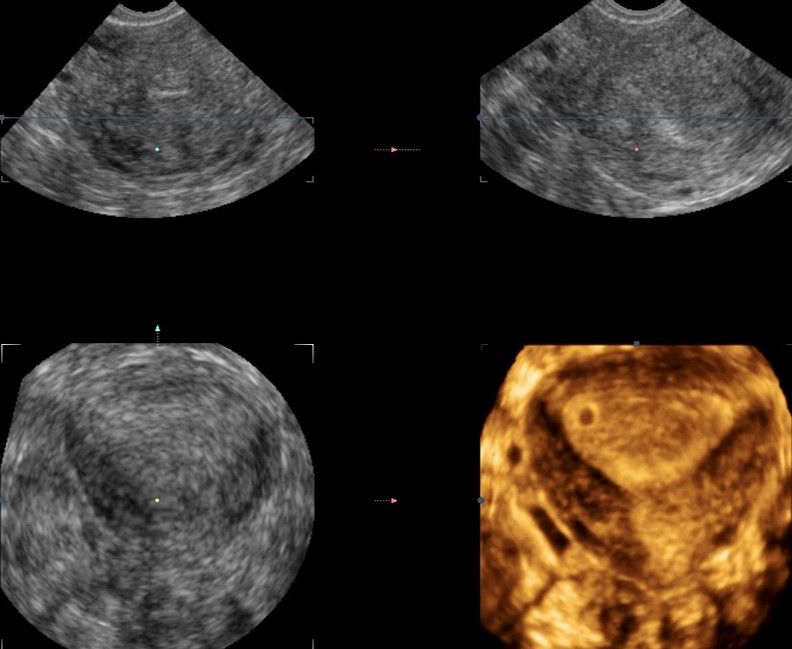

Современные экспертные УЗИ сканеры дают возможность проводить исследования всех органов в 3D. Это позволяет, используя полученный массив данных, получать диагностические сечения в любой плоскости, недоступной для обычного 2D УЗИ. Наиболее интересной является фронтальная. Например, визуализация полости матки. Диагностическая возможность выявления пороков развития превосходит все другие методы (рентгеновские и МРТ). Метод также позволяет уточнить положение ВМК (спирали) в полости матки, расположение миоматозных узлов, расположение плодного яйца на малых сроках, полипов. Сегодня современное экспертное ультразвуковое исследование невозможно без использования 3D УЗИ.